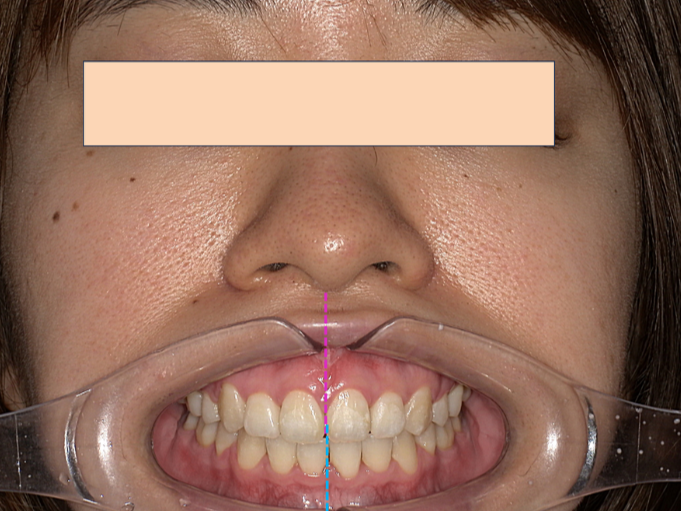

この患者様は、歯の凸凹も気になるが、一番は口元の突出を改善したい、とのことでした。

この方の場合は上下の骨格の関係も二級関係(上顎が若干前・下顎が若干後ろに位置している)もありましたが、最も顕著だったのは、上下の前歯の歯の軸が上下ともに前に倒れていることでした。

注目していただきたいのは前歯の角度です。

上下の前歯が作る角度(インターインサイザルアングル)が99°でした。

99度ってどうなの?」と思われるかもしれませんが、理想的な美しさとされる角度は約120度〜130度と言われています。つまり、99度というのは「前歯がかなり外側にパタンと倒れて、突き出している状態」なんです。

この角度が深くなる(120〜130度に近づく)ことで、唇がスッと中に入り、横顔のEラインが整います。数字で見ると、矯正でどれだけ歯の土台から角度が変わったかが一目瞭然です。